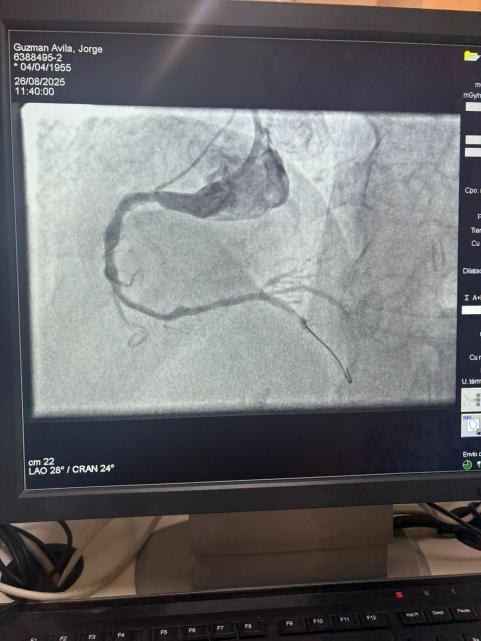

Nous sommes fiers de partager un cas remarquable de l'Hôpital Sótero del Río, Chili, où le Dr Martín Valdebenito a traité avec succès une lésion fortement calcifiée dans l'artère coronaire droite (première courbe) en utilisant notre système de cathéter de dilatation coronaire IVL Vesscrack.

La procédure a obtenu des résultats exceptionnels, avec la région calcifiée effectivement fissurée et l'écoulement du navire restauré. Cela marque une autre étape importante dans l'élargissement de l'accès mondial à des solutions avancées pour la calcification coronarienne complexe.

La comparaison entre les images angiographiques pré-procédure et post-procédure démontre clairement l'impact clinique significatif de notre technologie IVL.